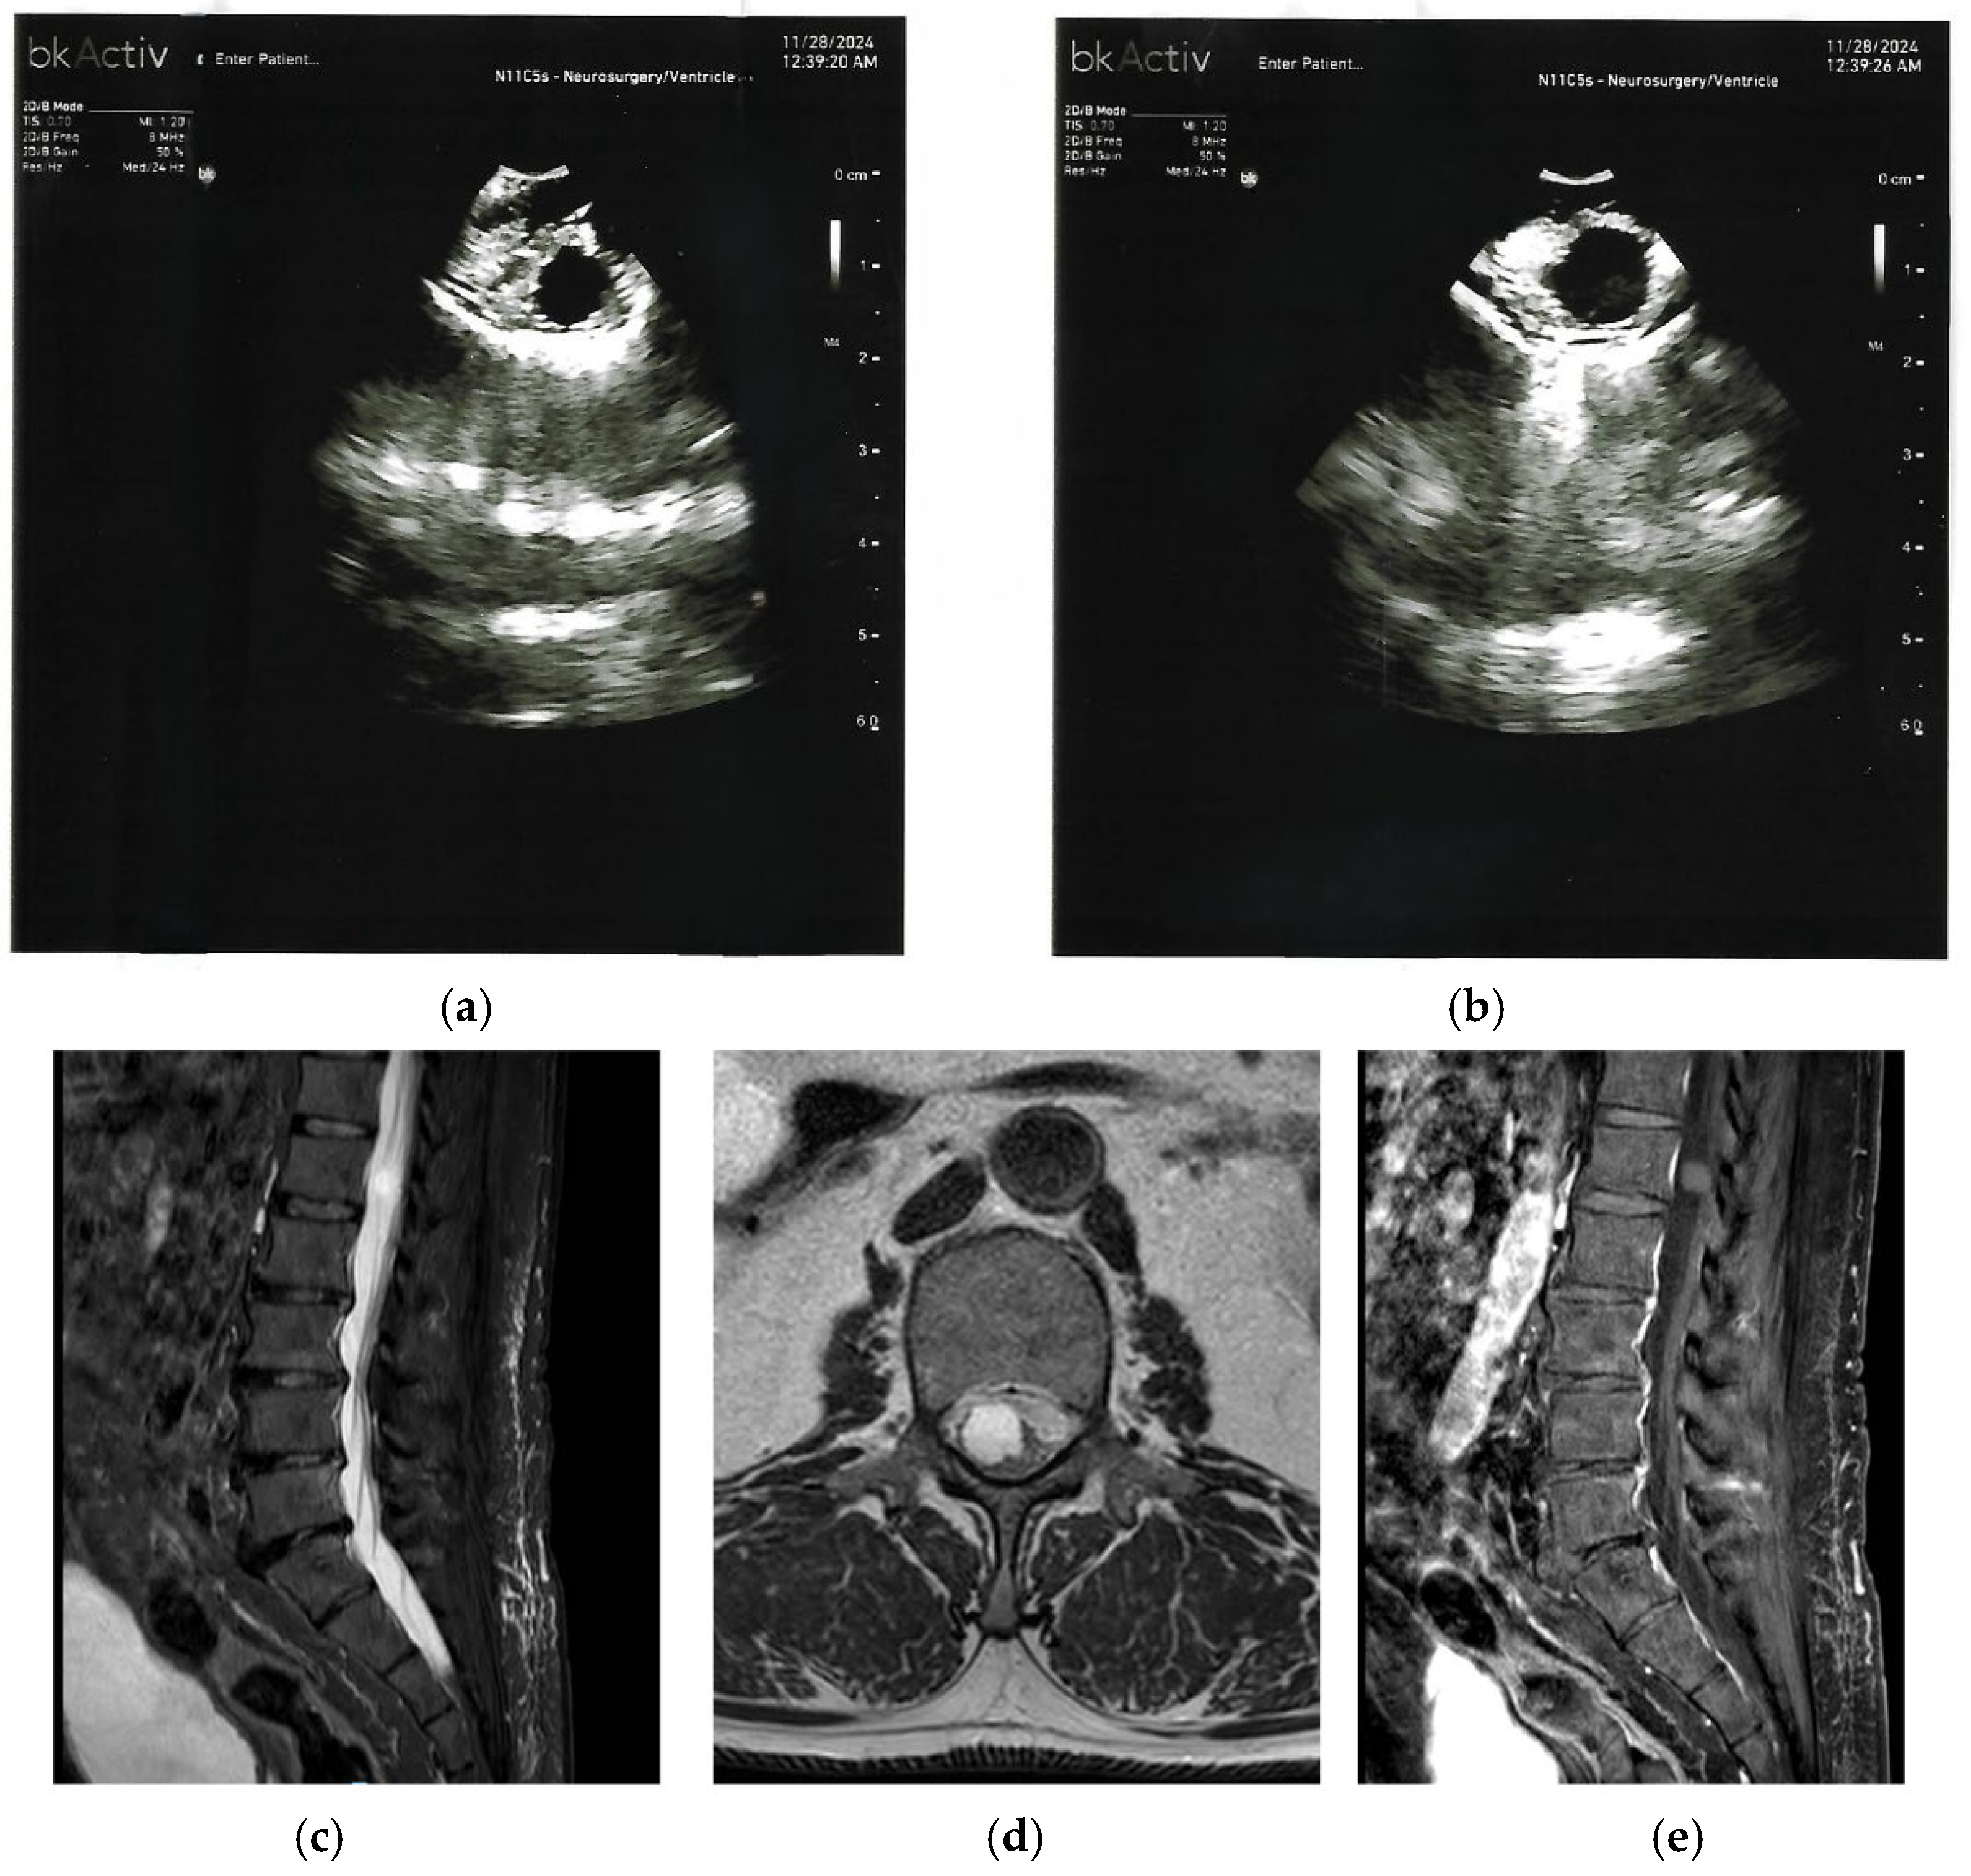

4. Spinal Cord Tethering

| Spinal Cord Tethering or Scarring | Focal dorsal cerebrospinal fluid loculation; anterior cord displacement (“scalpel sign”); adhesions or thickened filum. | Hyperechoic adhesions bridging dura and cord; effaced subarachnoid space; reduced cord excursion; stiffness reduction post detethering (for example, 93.84 kilopascals to 9.35 kilopascals via shear wave elastography). |